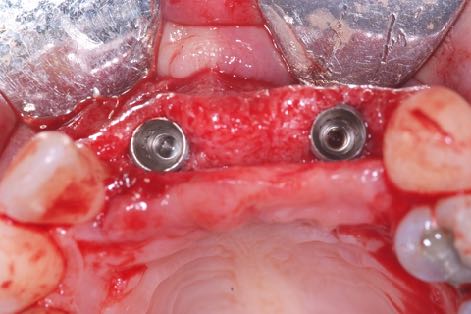

La stabilité primaire désigne la stabilité mécanique, la résistance initiale aux micro-mouvements et à la micro-mobilité d’un implant dentaire lors de l’insertion. Il existe plusieurs méthodes de mesure : évaluation subjective, couple d’insertion, analyse de la fréquence de résonance ou Periotest.

La stabilité secondaire désigne en revanche la stabilité biologique, ou ostéo-intégration. C’est elle qui détermine, en dernier lieu, la capacité de la restauration implanto-portée à supporter les forces fonctionnelles et à jouer un rôle pleinement fonctionnel dans la dentition d’un patient.

Il faudrait se concentrer sur la stabilité secondaire et l’obtenir le plus vite possible, en préservant en même temps la viabilité et la stabilité de l’os péri-implantaire, pour assurer la réussite clinique de l'implant à long terme.

Je suis convaincu que le maintien de l’os marginal péri-implantaire est l’un des facteurs clés de prévention des complications biologiques futures. Par conséquent, si l'on arrive à obtenir une stabilité secondaire en minimisant les lésions osseuses au niveau cellulaire, les conditions d’une réussite prévisible durable sont presque entièrement remplies.